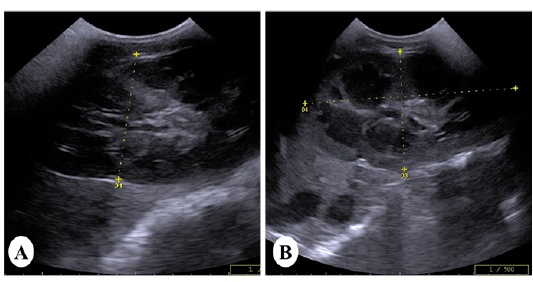

Ultrasound images of the kidney of vitamin K3-exposed horses showing (A); enlargement of the right kidney with loss of differentiation between cortex and medulla whereas, the left kidney showing increasein the echogenicity of the renal cortex making the corticomedullary junction more prominent (B)